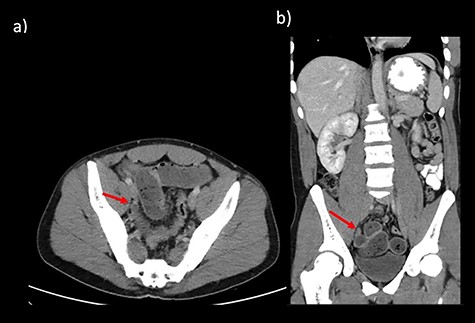

CT abdomen findings from Cases 1 and 2 showing distal SBO with the transition point in the pelvis. (a) Case 1 CT axial view. (b) Case 1 CT coronal view.

Case 1 is a 24-year-old male with a virgin abdomen who presented with a 3-day history of crampy abdominal pain and vomiting. He was haemodynamically normal and afebrile. He had tenderness in the lower abdomen and no peritonism. There was a moderate leukocytosis with a WCC of 12.7 × 109/L. An abdominal CT demonstrated distal SBO and a transition point located in the right pelvis and a small amount of free fluid (Fig. 1). The appendix was identified as normal. On Day 0 of his admission, he underwent a diagnostic laparoscopy. Intra-operatively, an MD was found at the site of the transition point between small bowel dilated proximally and collapsed distally (Fig. 2). Enteric contents were thickened raising the possibility of a faecolith. Macroscopically, the MD appeared to be normal, with no features of intussusception, volvulus or inflammation at the site. The MD was exteriorized through a mini-laparotomy and small bowel resection with a side-to-side stapled anastomosis was performed. Histopathology revealed MD with no features of inflammation or ectopic mucosa.